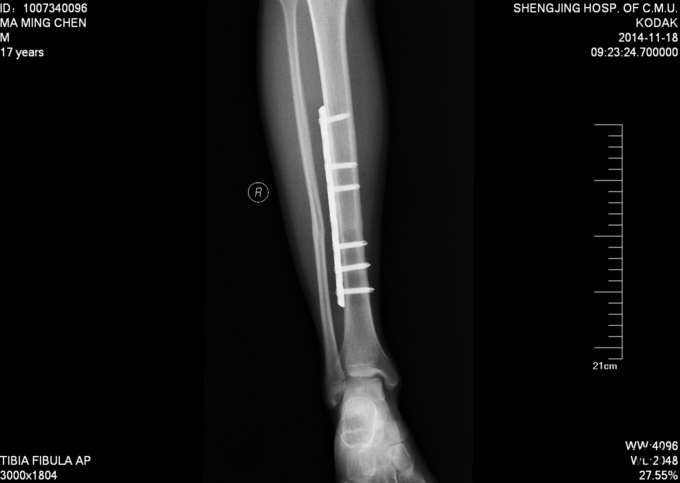

现病史:患者及家属自诉于2013年11月9日下午2点因打篮球摔伤致右小腿疼痛、肿胀,后于2013年11月11号于我院行胫腓骨骨折切开复位内固定术,现内固定物固定已一年半来我科继续治疗。病来无发烧发热,无咳嗽,无其他不良主诉,饮食二便正常,体重近期无明显变化。

患者入病房,右小腿处可见一约10cm瘢痕,瘢痕部无明显压痛,右下肢无轴向叩击痛,无明显肿胀,足趾背伸跖屈肌力5级,足背部及小腿感觉正常,双下肢等长。足背动脉可触及搏动。其余肢体未见异

入院后完善检查,及功能检查后,于全麻下行右胫腓骨骨折术后内固定物出去术,术后第二天换药示切口无红肿渗出,患者自动退院。